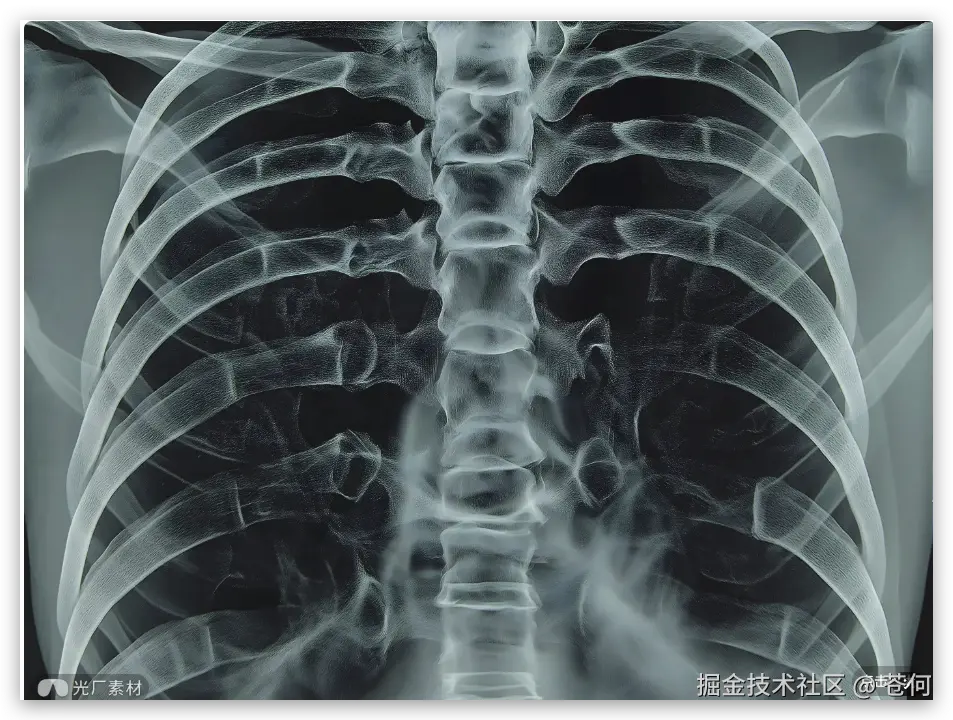

医疗影像分析

VLM 视觉模型另外一个使用场景就是在对医疗影像进行分析,比如:

提示词:这是一张胸部X光片,请检查一下肺部是否有异常结节。如果发现可疑区域,请圈出来,并大致测量一下它的最大径。另外,这张片子有点歪,请帮我把它旋转扶正,让脊柱保持垂直,看下效果。

Doubao-Seed-1.6-vision 就会依次自主调用工具,先是调用rotate进行旋转,

然后调用 zoom 工具进行局部多次放大:

视频如下: